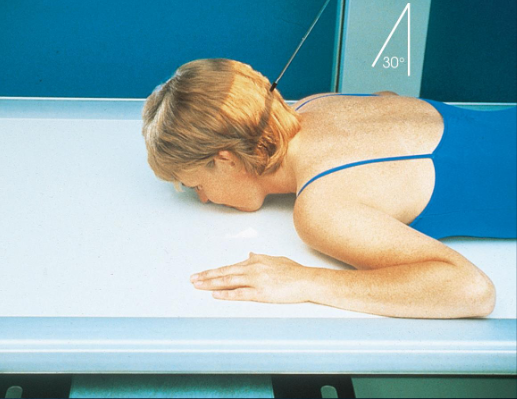

PA axial mandibular rami

patient position:

prone or upright

part position:

forehead and nose resting on Bucky/table

OML perpendicular to IR

MSP perpendicular to IR

respiration suspended

CR:

20-25 degrees cephalad, exits acanthion

collimation:

1 inch beyond the lateral sides, above the TMJs, and below the chin